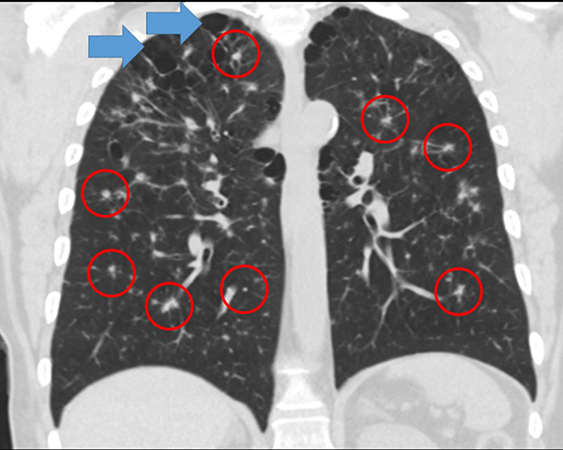

Clinical History: A woman in her 60s presented with cough. Chest CT showed moderate emphysema, reticulonodular changes bilaterally, and numerous bilateral irregular and spiculated nodular densities scattered throughout both lungs (Figure 1) significantly increased in size and number since a CT performed 4 years prior (a lung biopsy performed at that time had been non-diagnostic). There was radiologic concern for metastatic disease or an atypical infectious process. Her pulmonary function tests show mild obstruction, no restriction and mildly reduced DLCO. She was a 30-pack-year current smoker. A second CT-guided core needle biopsy was performed. Photomicrographs from the biopsy are shown in Figures 2-4 (Figures 2 and 3: H&E, Figure 4: CD1a).

The usual chest x-ray findings are diffuse bilateral reticulonodular infiltrates with normal or increased lung volumes. Chest CT findings include bilateral lung nodules that are often centrilobular, cavitary and are almost invariably tiny (millimeter-sized). They may be so numerous as to raise the possibility of disseminated mycobacterial or fungal infection or disseminated malignancy on imaging. This differential diagnosis often prompts a lung biopsy. Bilateral thin-walled cysts may also occur. These are usually - but not always - bilateral and upper and mid-lung predominant. Relative sparing of lung bases is often cited in the imaging literature. Bilateral ground-glass opacities, probably attributable to macrophages and/or smoking-related interstitial fibrosis (SRIF). Theoretically, the combination of nodules and cysts might be so characteristic that the diagnosis can be made on the basis of chest CT alone and biopsy can be avoided. In practice, although radiologists often suggest the diagnosis in classic cases, most cases are biopsied for confirmation. Pathology is the gold standard for this diagnosis.